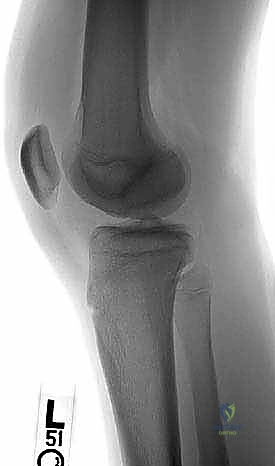

2. التصوير بالأشعة السينية (X-rays)

هي الخطوة التصويرية الأولى والأساسية. يطلب الدكتور هطيف صوراً بوضعيات محددة (أمامية خلفية، جانبية، وضعية النفق Notch view، ووضعية شروق الشمس Skyline view) أثناء الوقوف (تحميل الوزن). تساعد الأشعة السينية في رؤية العيوب العظمية، وتحديد حجم الآفة، واكتشاف أي أجسام حرة (Loose bodies) متكلسة داخل المفصل.